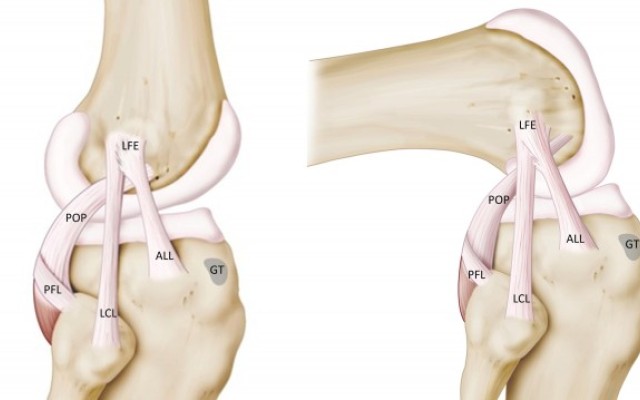

The anterolateral ligament(ALL) is a ligament on the lateral aspect of the human knee, anterior to the fibular collateral ligament. Perhaps the earliest account of the ALL was written by French surgeon Paul Segond in 1879, in which he described a ligamentous structure between the lateral femur and tibia.

The ALL, which has been suggested to occur in at 33-97% of...